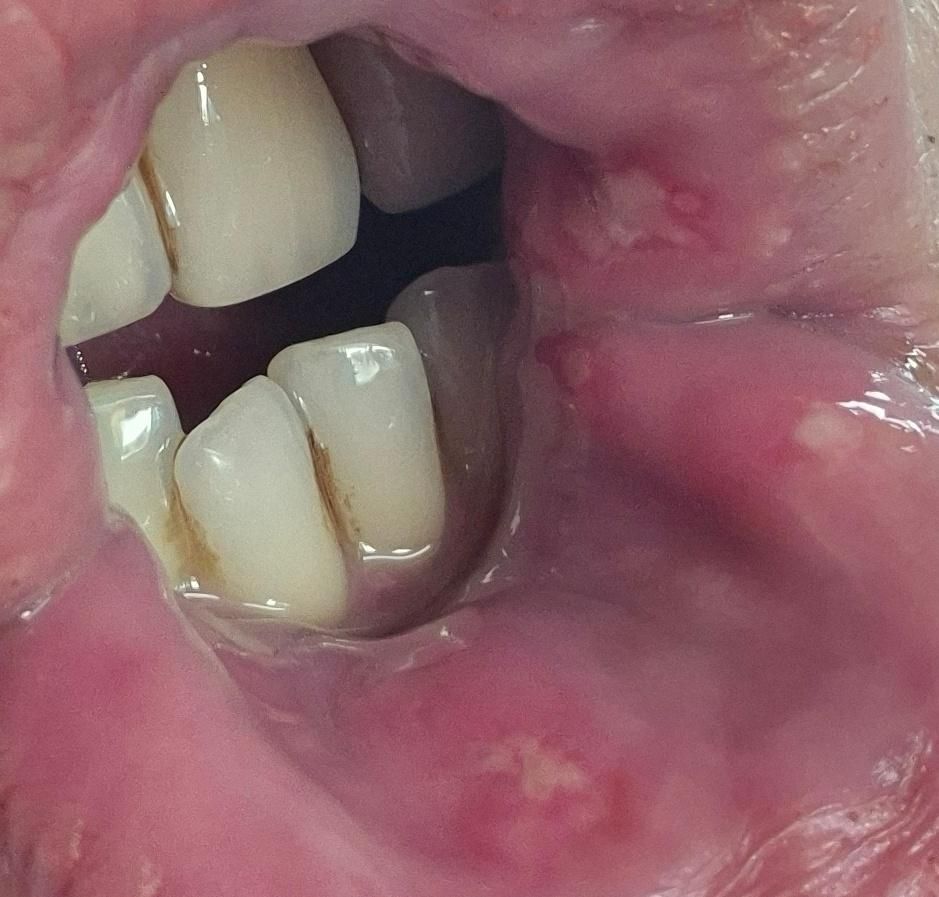

• 3번 째 사진